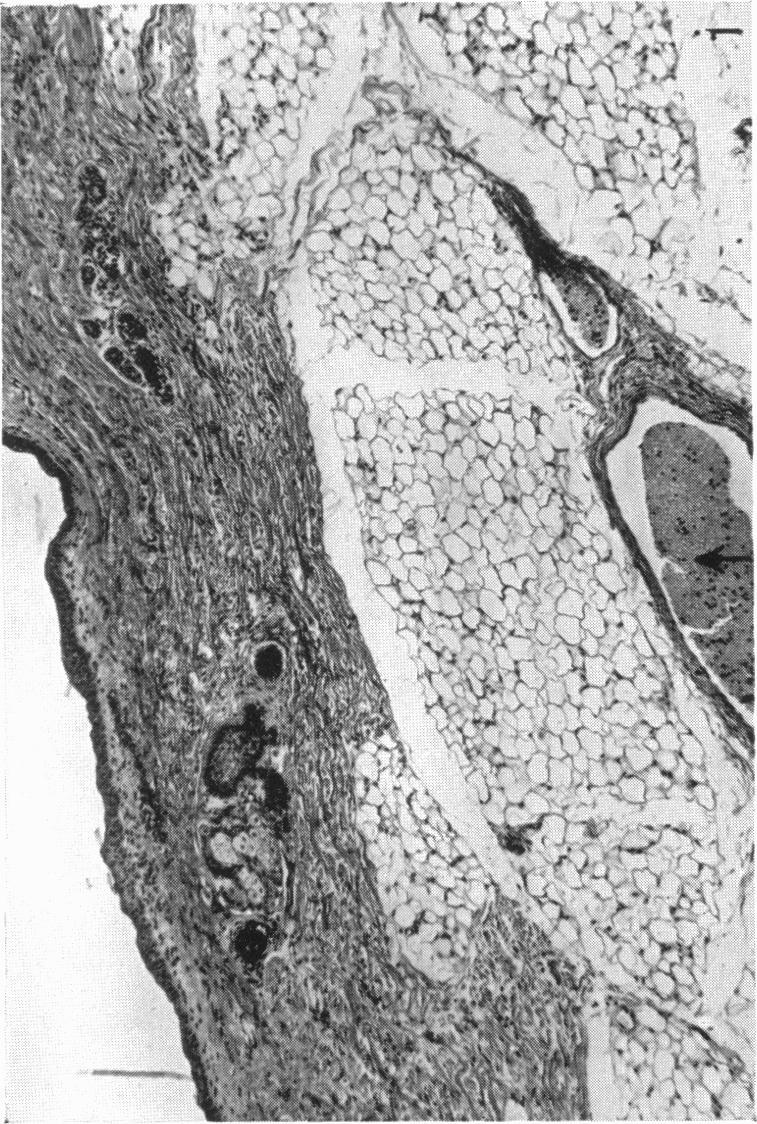

The So-called Interscapular Gland and Tumours Arising Therein.